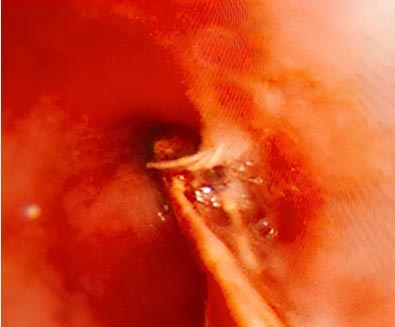

气道内异物位置镜下视图

术中,陈燏先通过硬镜精准抵达异物所在位置,随后利用冷冻探头对虾体进行快速冷冻,使其与探头牢固黏连,再平稳地将异物完整取出。整个手术过程顺利,患者术后气道梗阻症状即刻缓解,生命体征平稳。